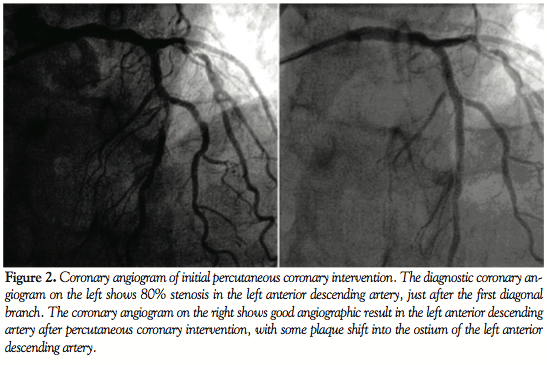

Eight months after the initial PCI, the patient complained of a recurrence of chest pains. We performed a diagnostic catheterization that showed ISR of the BMS in the LAD. Furthermore, progression of the side branch stenotic lesion was observed, resulting in a bifurcation lesion with both distal main branch and side branch involvement (ie, Medina Class 0.1.1, Figure 3).